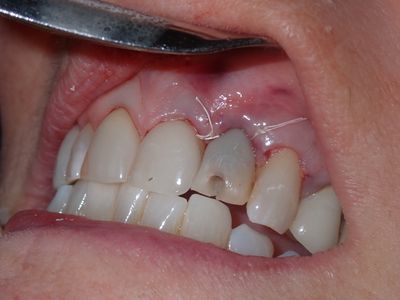

Atraumatic exo, loss of labial plate mid root about 2-3mm, CEJ and apical bone intact, region of thinner Labial-palatal bone, flapped site. osteotomy underprepared, implant placed with excellent stability. Buccal and socket grafted with 90/10 mix of mineralized cortical/xenograft followed by collagen membrane outside of socket on buccal, implant loaded with temporary crown out of centric and protrusive occlusion